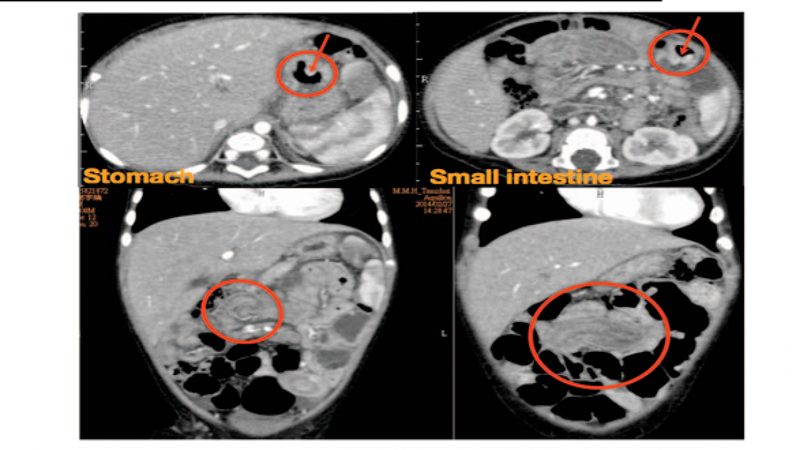

Đối với người mắc JPS, polyp thường phát triển trong độ tuổi 20 tuổi. Số lượng polyp mà một người có thể có trong đời dao động từ khoảng 5 đến hơn 100. Hầu hết các polyp đều lành tính (không ung thư), nhưng nó có thể làm tăng nguy cơ mắc ung thư đường tiêu hoá, chẳng hạn như ung thư dạ dày, ruột non, đại tràng và trực tràng trong các gia đình có JPS.

Hầu hết các polyp đều lành tính nhưng nó có thể làm tăng nguy cơ mắc ung thư đường tiêu hoáNhững người mắc JPS được xem là có nguy cơ mắc ung thư đại trực tràng, dạ dày, ruột non và tụy. Ước tính về nguy cơ ung thư chung liên quan đến JPS là từ 9% đến 50%, nhưng chưa xác định được nguy cơ đối với từng loại ung thư cụ thể.